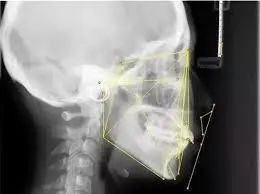

矫正前,拍摄牙齿全景片和头颅侧位X光片是必不可少的一步 | www.lovelytooth.com

接下来,我拍摄了曲面断层和投影侧位片以及全口牙齿锥形束CT,用于描绘标志点进行线角的测量,后用3D扫描仪记录了牙齿的全貌,牙齿矫正的设计不仅包括表面上的牙齿排列、侧面像的协调,而且还要深入到骨骼结构、发育潜能、动静态的颌位关系。